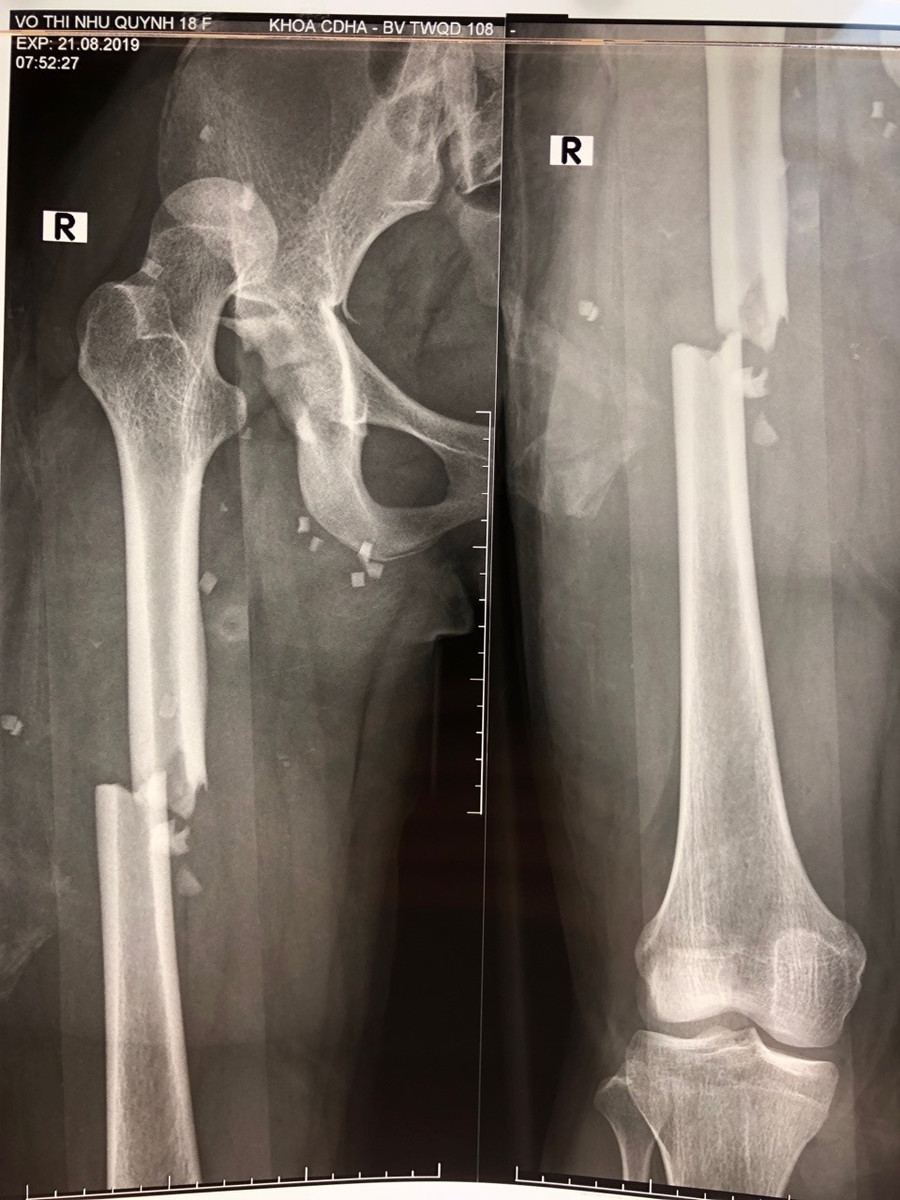

| Hình ảnh phim chụp. |

Tại bệnh viện 108, bác sĩ chẩn đoán sơ bộ bệnh nhân bị sốc chấn thương, gãy khung xương chậu: Gãy cánh xương cùng trái và sai khớp cùng chậu phải di lệch; gãy ngang ổ cối, sai khớp háng phải; gãy hở 1/3 giữa xương đùi phải, sai khớp hở khớp sên chày kèm gãy xương sên phải, gãy kín 1/3 giữa xương đùi trái do tai nạn giao thông.